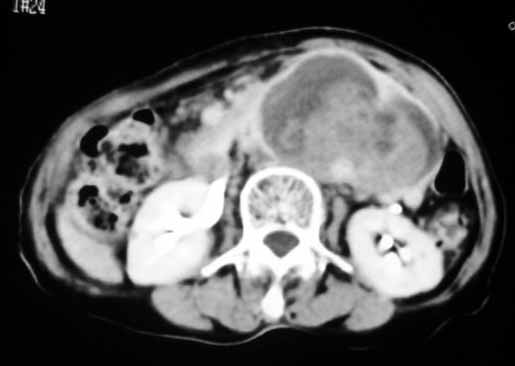

以下是引用天南地北在2007-4-30 17:42:00的发言:[br]增强扫描显示腹主动脉给包绕、推移。肿块不规则强化,[br]修正我在平扫的诊断[br]支持考虑:间叶源性肿瘤可能性大

以下是引用余辉在2007-4-30 18:01:00的发言:[br]病灶前方的条状增强影是什么?若是胰腺,位置似乎有点低,若是十二指肠,似乎又不诫该是那样强化,姑且将其看作胰腺吧,那么考虑来源于胰腺粘液囊腺瘤可能性大,其次考虑来源于肠系膜或者后腹膜的肿瘤如平滑肌肉瘤,异位嗜铬细胞瘤及淋巴瘤等。

以下是引用zyx168在2007-4-30 23:24:00的发言:[br]考虑:间叶源性肿瘤可能性大